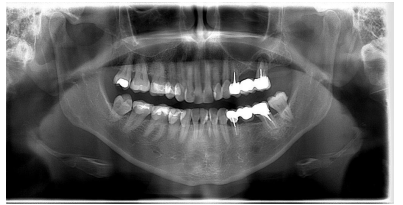

Se solicitó una radiografía panorámica con fines diagnósticos, evidenciándose la presencia de dos imágenes radiotransparentes, a nivel de 31 y sobre el 26. Sobre este último, se observó una lesión apical radiotransparente de forma ovalada de un tamaño de 10,68 mm de anchura y 9,80 mm de altura con límites bien definidos y contorno regular (Figura 1).

Tras estos hallazgos se aconsejó a la paciente la extracción del 26 conservando el 24. Una vez obtenido el consentimiento informado se procedió al corte de la prótesis, a nivel del 24 y posterior extracción del 26, sin complicaciones. Transcurridos cinco meses se volvió a solicitar un control radiográfico, en el que se observó la correcta remodelación de la zona, así como el déficit óseo para la rehabilitación con implantes (Figura 2).